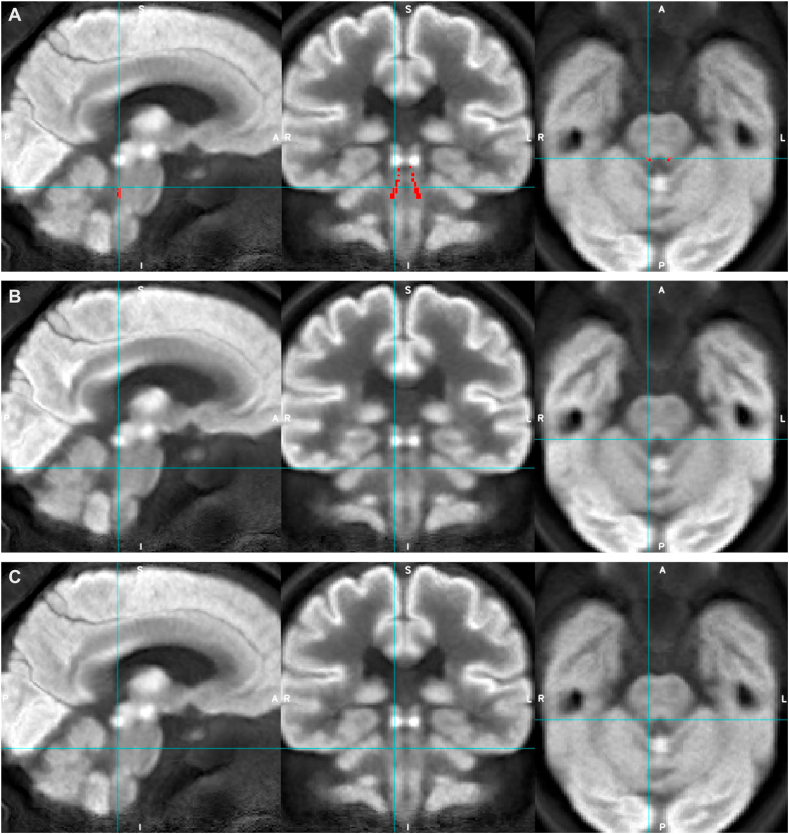

Fig. 1.

Example of the study co-registration accuracy protocol, which shows an individual’s co-registered FDG-PET images (at 3 different axial slices) and corresponding LC mask (Betts) position.

Fig. 4.

Appearances of the average group FDG-PET image for AD (rows A and C) and HC (row B) groups with Betts LC mask overlaid (red, row A, and blue crosshairs) to demonstrate LC ROI location.